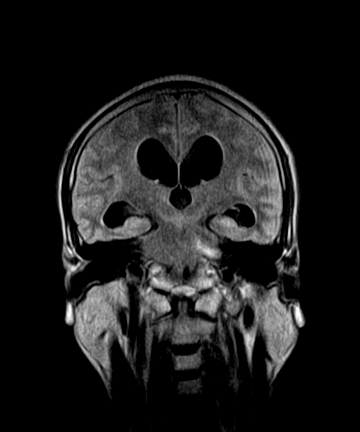

标题: MRI2064:少见病例。男性52,视力下降多年。 [打印本页]

标题: MRI2064:少见病例。男性52,视力下降多年。

四脑室区见混杂信号占位影,脑室系统扩张明显,临近结构显著受压称位,患者52岁,多考虑室管膜瘤可能性大

考虑第四脑室室管膜瘤并梗阻性脑积水;部分性空蝶鞍;左侧上颌窦粘膜下囊肿。

加左上颌窦囊肿

2、左侧上颌窦及蝶窦囊肿。

比较典型的脉络丛乳头状瘤并脑积水,鉴别小脑蚓部血管母细胞瘤。